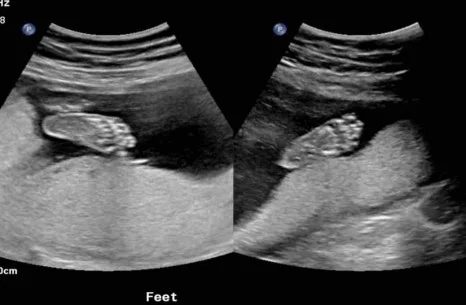

도시 이동을 해서 남편과 둘만 사는 보금자리로 이사를 가면서 입덧도 함께 사그라들었다. 내 집에서 일도 안 하고 내가 마음 편하게 있을 수 있다는 것 자체로 최고의 태교를 할 수 있었다. 영양제도 꾸준히 챙겨 먹고 가능하면 건강한 음식을 먹으려고 노력했다. 로토루아에는 맛있는 식당도 없고 제대로 된 한국 마트 없었기에 밥을 먹는 것에 어려움이 있신 했으나 한국에 갈 날만 손꼽아 기다리며 한 끼 한 끼를 버텼다. 20주가 넘어가면서 배가 조금씩 더 부르기 시작했고 27주 차에는 배가 상당히 나온 상태로 한국을 방문했다. 12시간 비행에 걱정을 많이 했으나 다행히 한국이 겨울이라 그런지 비행기에는 사람이 많이 차지 않아 누워서 올 수 있었다. 긴 비행으로 지친 몸을 이끌고 출구에 나오자 마중 나온 부모님이 우리를 기다리고 있었다. 여름옷을 입고 온 우리는 나름 패딩을 챙겨서 입긴 했지만 한국 1월 강추위에 주차장까지 걸어가는 그 짧은 순간 사이에 정말 너무 추워서 온몸이 부들부들 떨렸다.

나는 뉴질랜드에서 출산을 하지만 아이는 뉴질랜드와 한국 이중국적을 갖게 된다. 태어나기도 전에 이중국적에 영어와 한국어를 모국어로 장착하게 될 이 아이가 부디 건강하게만 태어나길 바라는 마음이다.